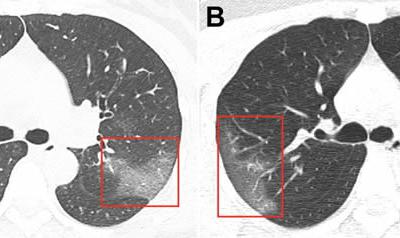

中国卫生部门公开一名感染2019-NSV冠状病

中国卫生部门公开一名感染2019-NSV冠状病毒的女性患者的肺部图片( © 照片 : ...